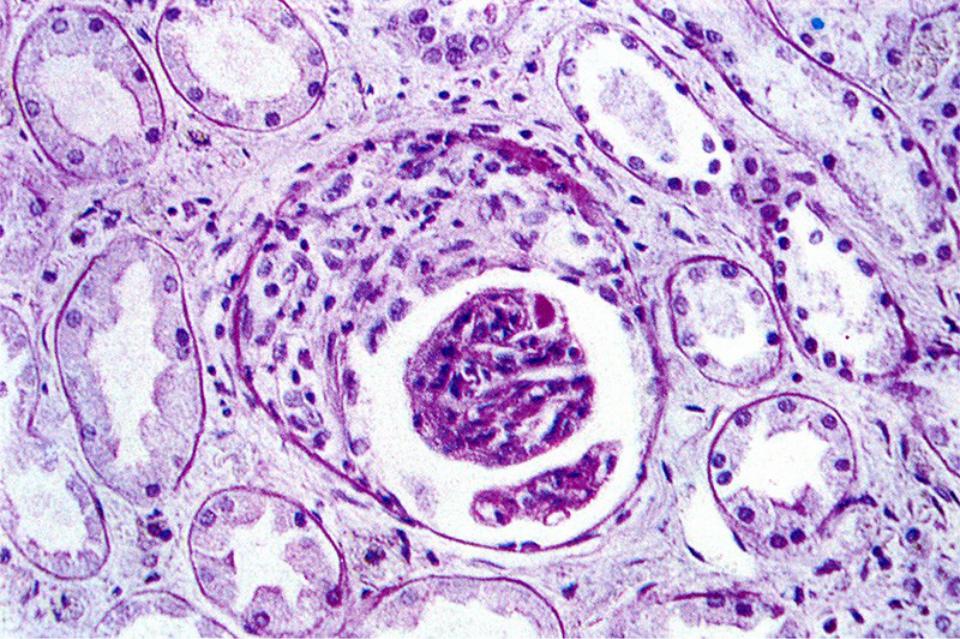

Механизм остро го диффузного гломерулонефрита